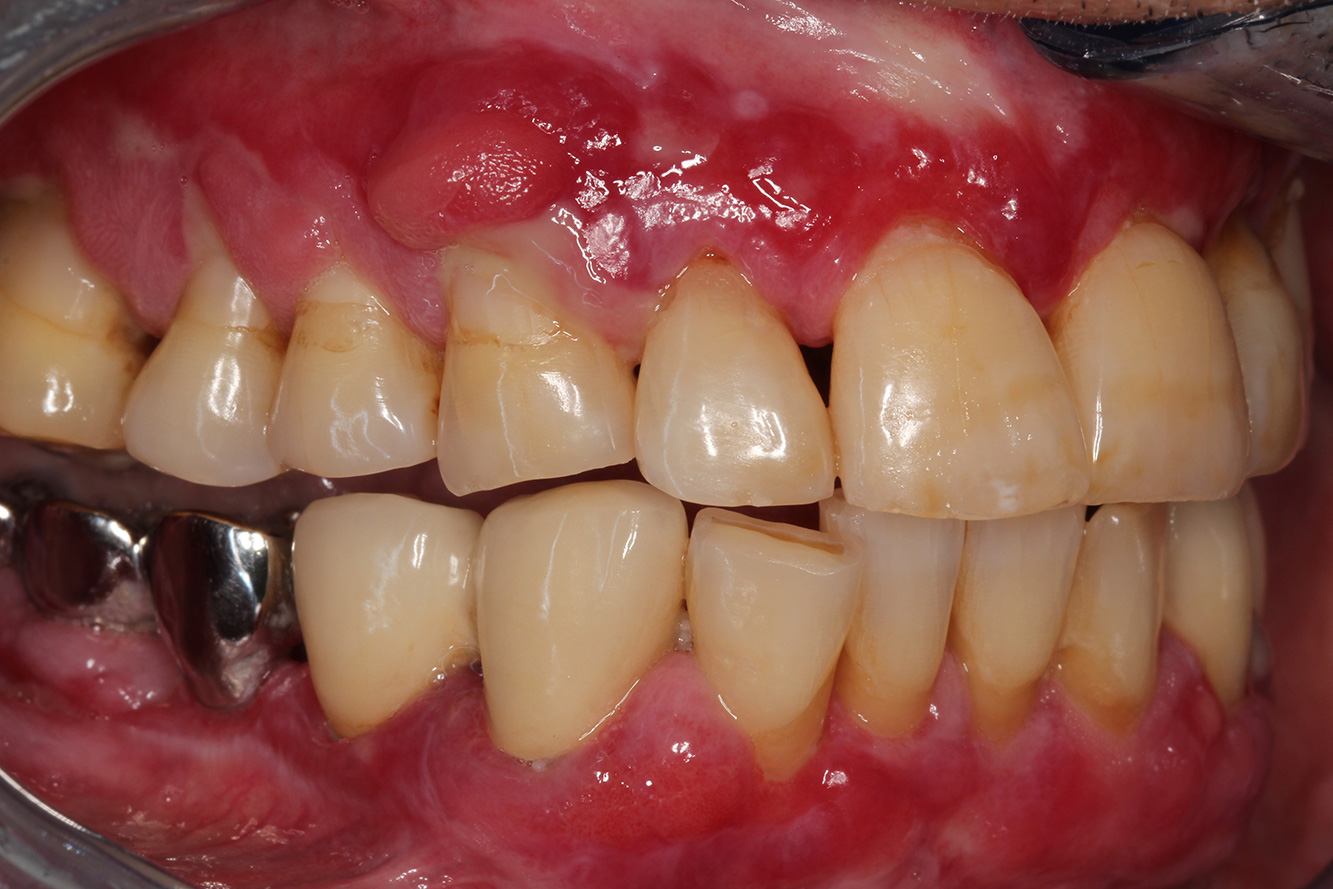

A 71-year old patient presents with having previously undergone a kidney transplant and with a history of hypertonia (high blood pressure). Due to his medical history, long-term medication with cyclosporine is required to suppress the immune system, as well as amlodipine to lower blood pressure. The patient also reports sensitive and bleeding gums. From an oral health perspective, the patient has undergone dental restoration and has eight missing teeth, pronounced gingival growth, and grade B, stage II periodontitis with active pockets and initial root caries on tooth 22. The caries risk assessment determines a moderate risk of caries (API 60). The following treatment recommendations can be determined for the prophylaxis session.

Based on the patient’s medical history, it is possible to identify a particular risk of complications. Due to the kidney transplant, the patient is immunosuppressed (cyclosporine), and therefore has a weakened immune system and requires infection prophylaxis (recommendation: 2 g of amoxicillin as an antibiotic, 1 hour before the session). At the same time, the patient’s long-term medication carries an increased risk of disease, as the gingival overgrowths identified are associated with this medication (20).

The patient’s situation must be addressed, especially when it comes to motivation and instruction. Due to the gingival overgrowths, the patient finds it difficult to practise good oral hygiene at home. The increased susceptibility to infection as well as the progression and emergence of the overgrowths (22) should be discussed at the patient’s level. At the same time, the patient should be instructed in hygiene techniques that are tailored to his individual needs.

A shorter recall interval of three to four months is recommended for this patient. This is mainly due to the gingival overgrowths associated with the patient’s medication, the fact these overgrowths make at-home oral care difficult for the patient, and the risk of progression of periodontitis.